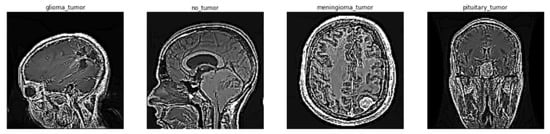

3.1. Image Pre-Processing